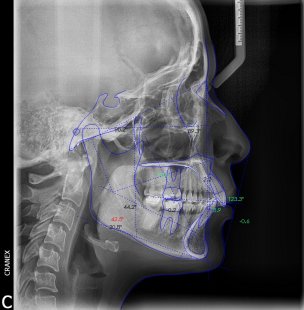

Inicio / Servicios / Análisis radiológico computarizado